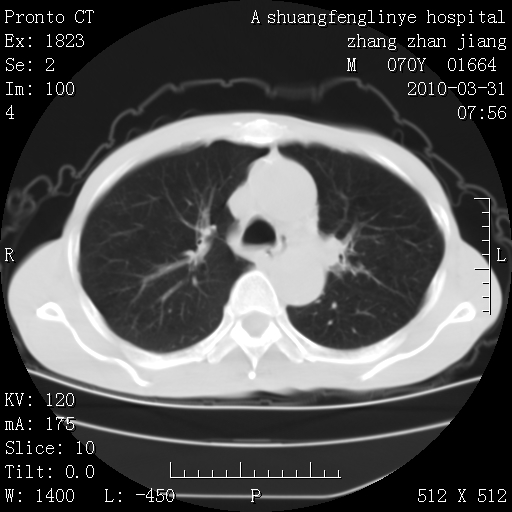

双上肺继发型tb并左上空洞形成,主动脉冠脉钙化。

支持:继发性肺结核伴空洞形成!建议纤支镜检查待出外周围型肺癌可能!

1)两肺上叶继发性肺结核并左肺上叶空洞形成。2)冠状动脉及主动脉钙化。